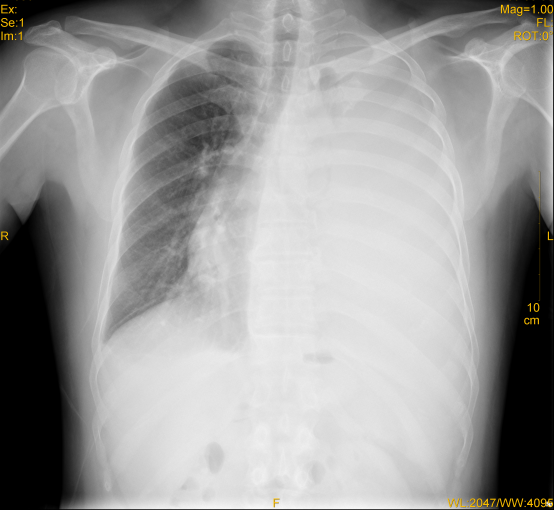

患者完善血常规、凝血功能、胸片检查,结果如下: 血常规:白细胞 24.5×109/L,N 95%,红细胞 3.65×1012/L,血红蛋白122g/L。 凝血功能:凝血酶时间(TT):16.6s 凝血酶原时间(PT):10.9s 活化部分凝血酶时间(APTT):26.3s 胸片:  患者下一步该如何处理?